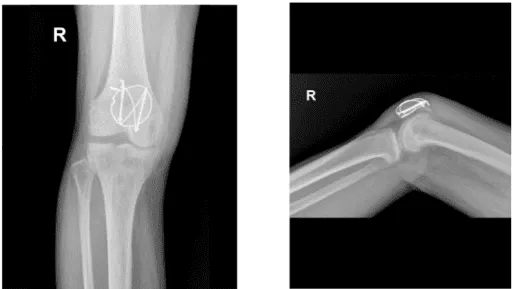

X-ray Image right knee

The fracture received a thorough irrigation. The fracture was reduced and secured with a clamp. After creating a short vertical incision to the patellar tendon, two K-wires were transferred from the distal bone to the proximal bone once the fracture was securely stabilized. After measuring the K-wires, two cannulated cancellous screws were medially and laterally placed over the K-wires to accomplish fixation.

The anterior patellar surface was then perforated by making a figure-eight with an 18-gauge stainless steel wire after it had been threaded through the two screws. The wires were tied super laterally with a knot that was secured.

Due to osteoporosis, there was some comminution and the lateral screw was moved proximally by the wire. A cerclage wiring was applied to the 18-gauge wire once more to support the fixing. A satisfactory fixation was attained once the cerclage was finished and the knot was tightened super laterally.